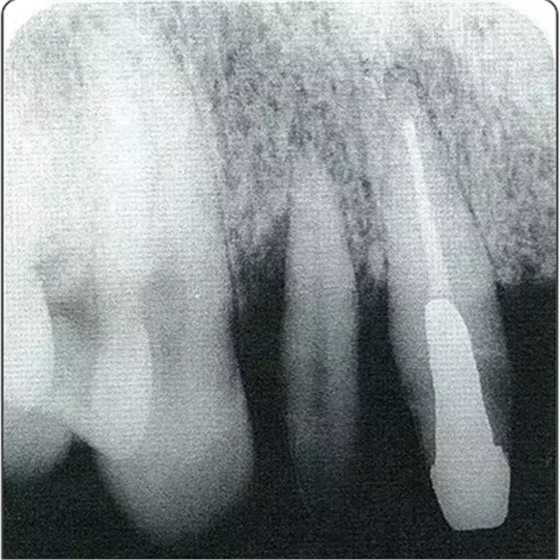

圖10-2 x片顯示的遠中部有垂直性骨缺損。